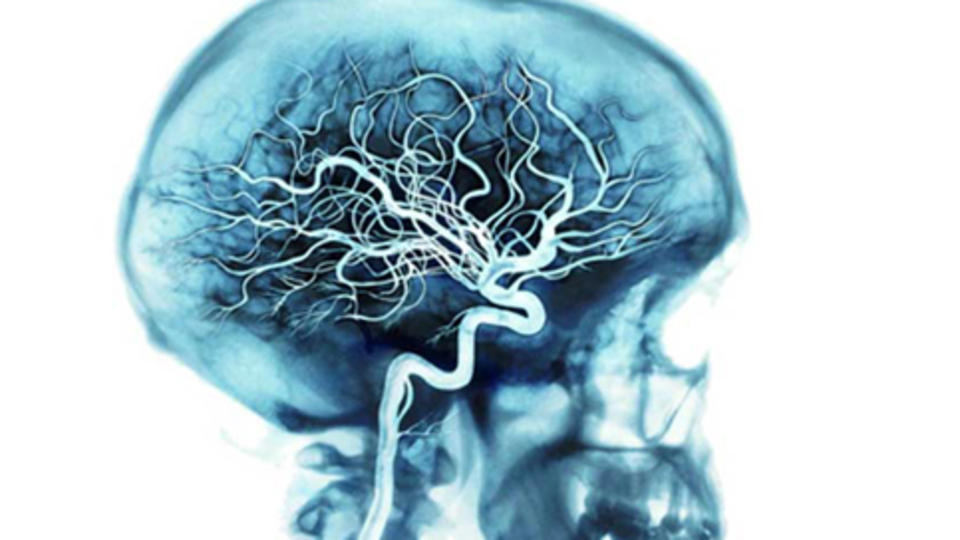

ANEVRİZMANIN BİLİNMEYEN TEHLİKESİ!

Damar hastalıklarını anlatan Prof. Dr. Murat Aksoy, ‘Anevrizma’ konusunda önemli bilgiler verdi. Uygulamalı olarak anevrizmayı anlatan Prof. Dr. Murat Aksoy, özellikle sigara içen kişilerin bu hastalığa dikkat etmesi gerektiğini ve anevrizmanın patlaması durumunda acilen müdahale edilmesi gerektiğini söyledi.